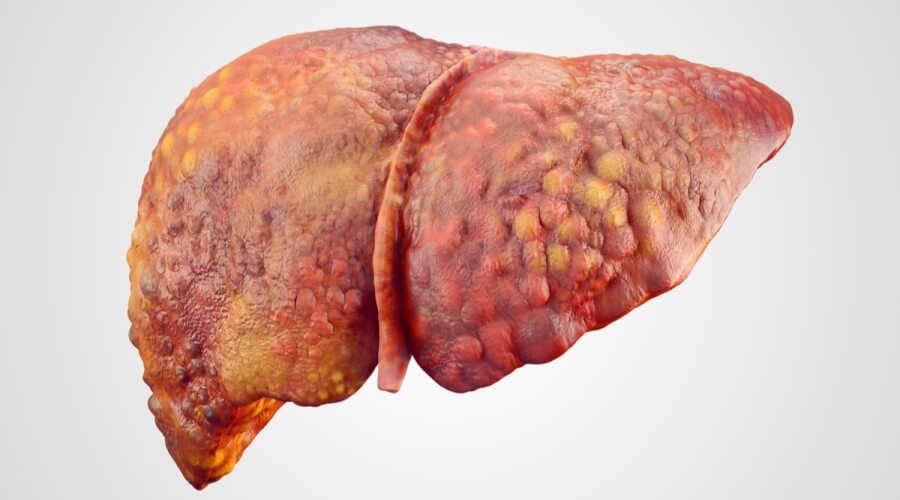

- تليف الكبد "تشمع الكبد"، يعد السبب الأكثر شيوعًا لارتفاع ضغط الدم البابي؛ إذ يؤدي تندب أنسجة الكبد إلى إعاقة تدفق الدم عبره. وينتج التليف عادة عن:

- وأيضًا الإصابة بفيروس التهاب الكبد B أو C.

- وكذلك تعاطي الكحول لفترات طويلة.

- وقد يرجع السبب لبعض الأمراض الوراثية أو المناعية التي تؤثر على الكبد.